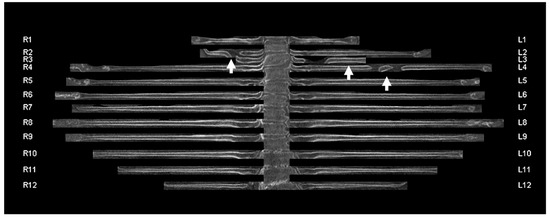

2.2. CT Acquisition and Post-Processing

2.3. Image Analysis